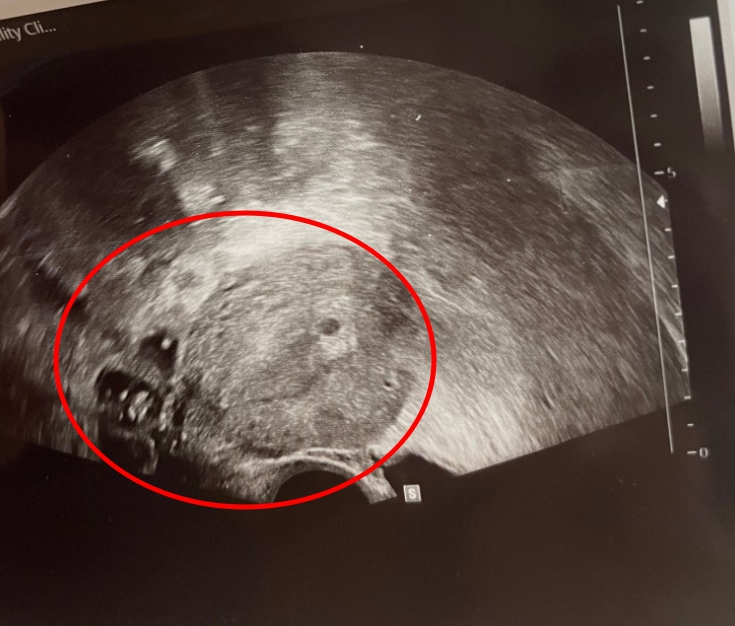

아프리카TV BJ 겸 유튜버로 활동 중인 유혜디(본명 송아리)가 미스틱 진성준의 아이를 임신했다가 낙태를 했다고 블로그에 고백했습니다. 유혜디 임신 22주차에 중절 수술을 받았고 밝히며 남친 M이라 밝힌 미스틱 진성준과 주고받은 카톡, 아이 초음파 사진 등을 공개해 파장이 일고 있습니다. 이에 유혜디 방송 휴방 이유 역시 팬들이 이해하고 있는 상황에서, 그가 방송을 쉬며 남긴 공지가 재조명되며 팬들이 안타까워하고 있습니다.

앞서 유혜디는 자신의 네이버 블로그에 팬들에게 미안하다는 말을 하며 글 4개를 작성해 올렸습니다. 유혜디 블로그에 올라온 글에 따르면 그는 전 프로게이머 출신 인터넷 방송인 미스틱 진성준과 교제를 했고, 관계를 맺은 후 아이가 생겼다고 하는데요. 아이가 생긴 후 진성준 측은 지속적으로 임신 중절을 권유했고, 아이를 낳고 싶었던 유혜디는 어쩔 수 없이 시간이 한참 흐른 후인 임신 22주차에 반강제적으로 수술을 받아 아이와 이별했습니다.